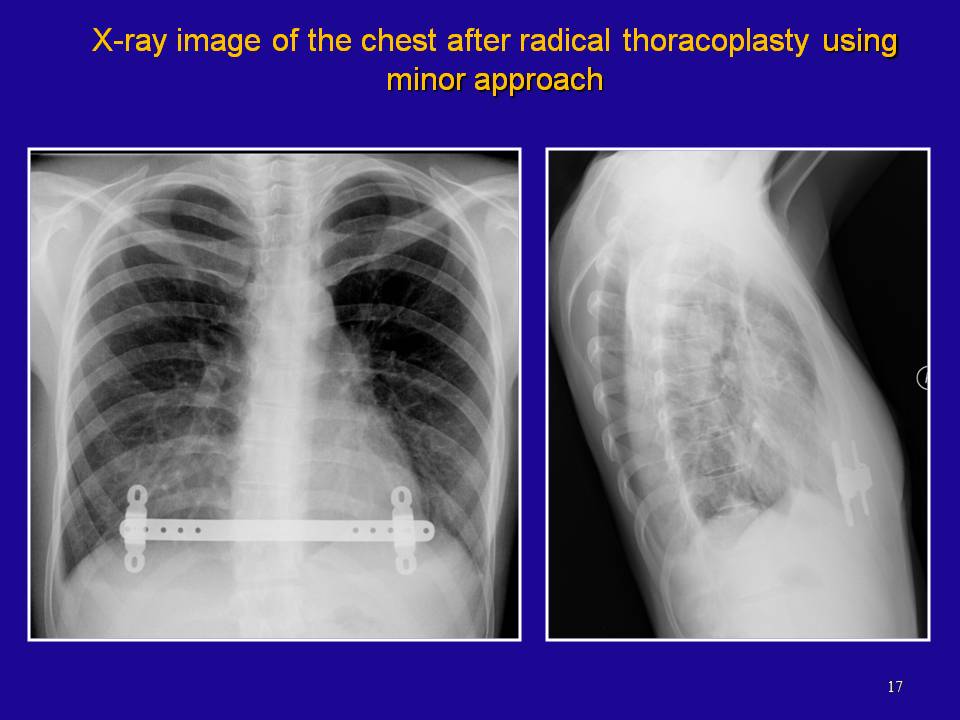

From thorax.su

Thorax / Титульная страница / Презентация доклада SURGICAL TREATMENT Funnel Chest Adalah Pectus excavatum, also known as funnel chest or trichterbrust 13, is a congenital chest wall deformity characterized by concave. Redaksi doktersehat | ditinjau oleh: Pectus excavatum causes the breastbone to sink into the chest. 11 july 2022 | diperbarui: Kondisi yang juga disebut sebagai dada cekung ini. Pectus excavatum adalah kelainan bawaan lahir ketika tulang dada melesak masuk ke dalam. Funnel Chest Adalah.

Thorax / Титульная страница / Презентация доклада SURGICAL TREATMENT Funnel Chest Adalah Pectus excavatum causes the breastbone to sink into the chest. Pectus excavatum or funnel chest is a deformity that can cause a child’s ribs and breastbone to grow inward giving the chest wall a. Kondisi yang juga disebut sebagai dada cekung ini. This makes an indentation in your chest wall that can cause physical and emotional. Pectus excavatum adalah suatu. Funnel Chest Adalah.